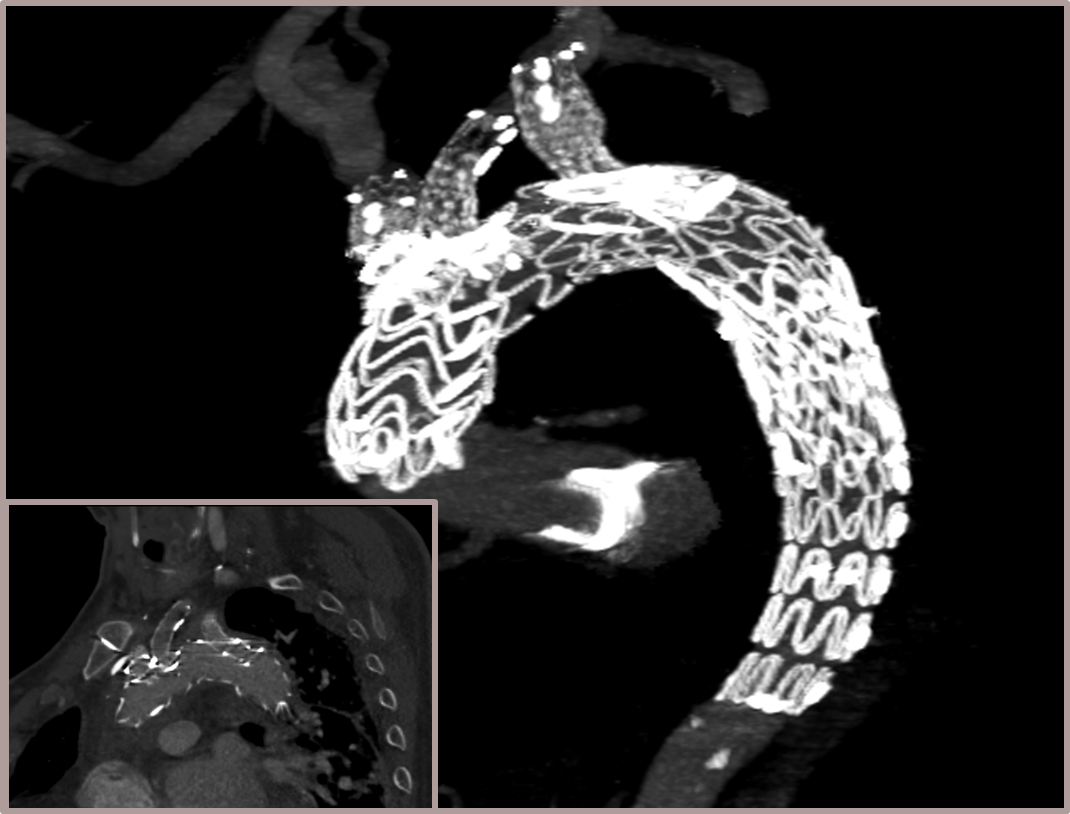

★ Case 1

男性,42岁,胸痛3天;

既往史:高血压,规律服用降压药物;

手术史:10年前外院行主动脉腔内修复+左颈总及左锁骨下烟囱支架植入;

夹层动脉瘤CTA:逆撕A型主动脉夹层,升主动脉及无名动脉见夹层累及,左颈总及左锁骨下动脉烟囱支架。

术前影像

剪除部分覆膜支架及左锁骨下烟囱支架

植入术中单分支支架

术中单分支支架开窗及加固

术后影像

术后CTA